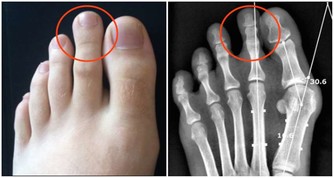

另外,護肝保健操也有裨益,做法是—— 第一步,揉大敦穴。盤腿端坐,赤腳,用左手拇指按壓右腳大敦穴(腳大趾甲根部外側),左旋按壓15次,右旋按壓15次。然後用右手按壓左腳大敦穴,手法同前。

第二步,按太衝穴。盤腿端坐,用左手拇指按右腳太衝穴(腳背第一、二趾骨之間),沿骨縫的間隙按壓並前後滑動,做20次。然後用右手按壓左腳大敦穴,手法同前。

第三步,揉三陰交穴。盤腿端坐,用左手拇指按壓右三陰交穴(內踝尖上3寸,脛骨後緣處),左旋按壓15次,右旋按壓15次。然後用右手按壓左三陰交穴,手法同前。